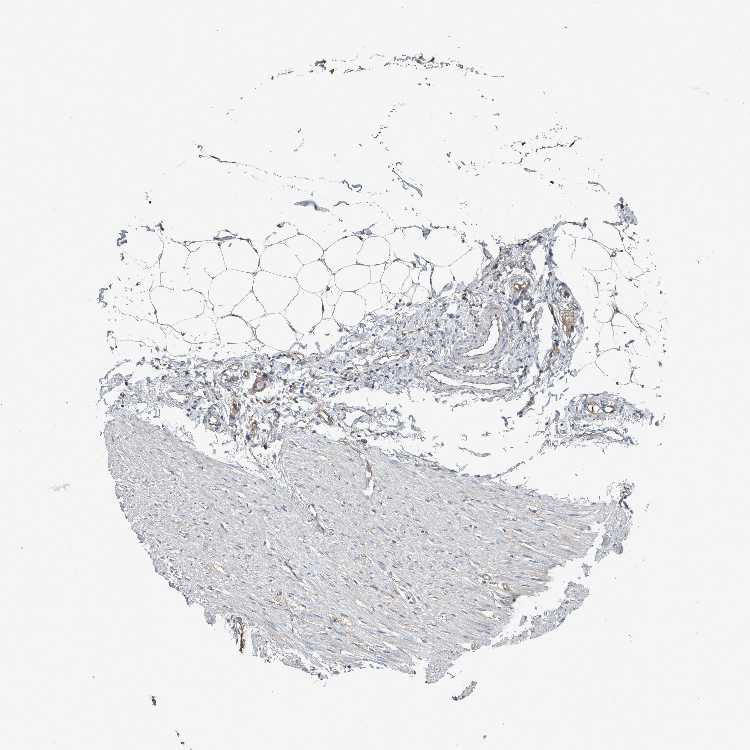

SOFT TISSUE 2 - Antibody stainingi

Antibody staining in the annotated cell types in the current human tissue is reported as not detected, low, medium, or high, based on conventional immunohistochemistry profiling in selected tissues. This score is based on the combination of the staining intensity and fraction of stained cells.

Each image is clickable and will lead to virtual microscopy that enables deeper exploration of all samples and also displays staining intensity scores, fraction scores and subcellular localization as well as patient and tissue information for each sample.

Antibody HPA026904

Fibroblasts Medium

Peripheral nerve Not detected